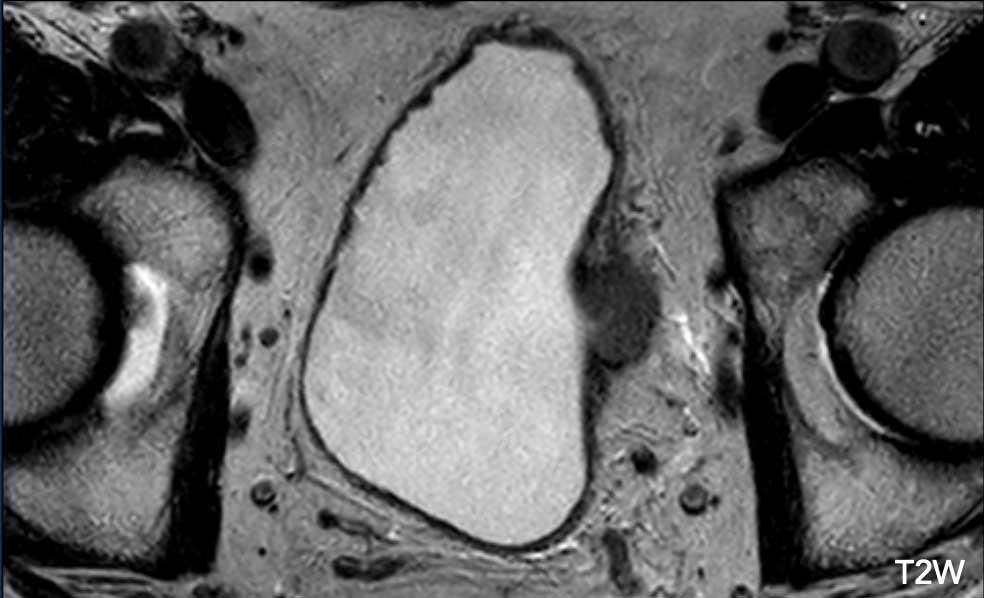

Hình ảnh

Có một khối u nhú không có cuống ở thành bàng quang bên phải.

Có thể thấy khối u xâm lấn mỡ quanh bàng quang vượt qua lớp cơ.

Đây là điểm T2W: 5.

Tiếp tục xem các hình ảnh tiếp theo…

Bước tiếp theo là đánh giá các hình ảnh DCE và khuếch tán để phân biệt giữa VI-RADS 4 và 5.

Tiếp tục xem các hình ảnh DCE và khuếch tán…